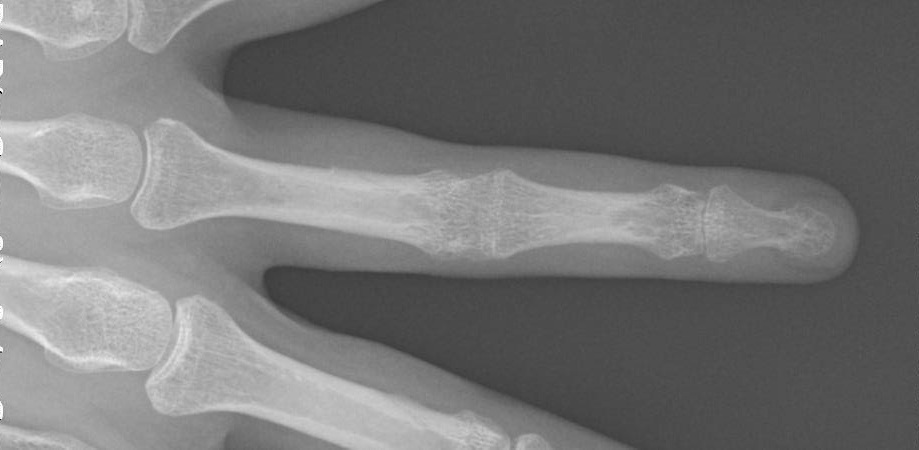

Клінічний кейс: травма пальця

Досить частою, особливо влітку, є травма пальців при грі у волейбол, футбол, баскетбол. Пацієнти приходять через декілька днів зі скаргами на біль в пальцях і обмеження розгинання.

Рентген іноді нічого не показує. Ушкоджені пальці мають характерну деформацію - «молоточок». Це відбувається внаслідок ушкодження сухожилка розгинача пальця.

В залежності від терміну та супутніх обʼєктивних даних пацієнту рекомендується або консервативне лікування (фіксація ортезом 24/7), або оперативне лікування.